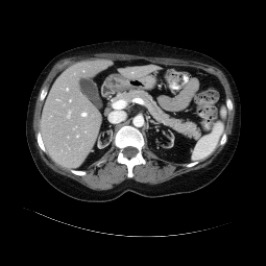

Integrating high-level semantically correlated contents and low-level anatomical features is of central importance in medical image segmentation. Towards this end, recent deep learning-based medical segmentation methods have shown great promise in better modeling such information. However, convolution operators for medical segmentation typically operate on regular grids, which inherently blur the high-frequency regions, i.e., boundary regions. In this work, we propose MORSE, a generic implicit neural rendering framework designed at an anatomical level to assist learning in medical image segmentation. Our method is motivated by the fact that implicit neural representation has been shown to be more effective in fitting complex signals and solving computer graphics problems than discrete grid-based representation. The core of our approach is to formulate medical image segmentation as a rendering problem in an end-to-end manner. Specifically, we continuously align the coarse segmentation prediction with the ambiguous coordinate-based point representations and aggregate these features to adaptively refine the boundary region. To parallelly optimize multi-scale pixel-level features, we leverage the idea from Mixture-of-Expert (MoE) to design and train our MORSE with a stochastic gating mechanism. Our experiments demonstrate that MORSE can work well with different medical segmentation backbones, consistently achieving competitive performance improvements in both 2D and 3D supervised medical segmentation methods. We also theoretically analyze the superiority of MORSE.

翻译:在医学图像分割中,整合高级语义相关的内容和低级解剖特征对于模拟这些信息非常重要。近期基于深度学习的医学分割方法已经显示出很有前景,可以更好地建模这些信息。然而,医学分割的卷积运算符通常在正则化网格上运作,这在本质上模糊了高频区域,即边界区域。我们在这项工作中提出了 MORSE,这是一个设计在解剖学水平上的通用隐式神经渲染框架,用于协助医学图像分割的学习。我们的方法的动机在于隐式神经表示已经被证明比离散化网格表示更有效地拟合复杂信号和解决计算机图形问题。我们方法的核心是将医学图像分割连续地对准粗糙的分割预测和模棱两可的基于坐标的点表示,并聚合这些特征来自适应地精细化边界区域。为了并行地优化多尺度像素级特征,我们借鉴了 Mixture-of-Expert (MoE) 的思想设计和训练我们的MORSE,使用随机门控机制。我们的实验表明MORSE可以很好地与不同的医学分割后骨干结合在一起,始终在2D和3D监督医学分割方法中实现了有竞争力的性能改进。我们还从理论上分析了MORSE的优越性。